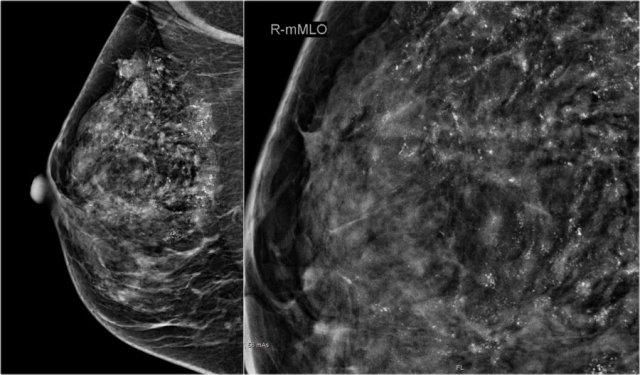

Đây là một ví dụ PET-CT khác.

Trên hình chụp nhũ ảnh, có một khối u kèm co rút da thứ phát.

Lưu ý nhiều vôi hóa dạng tuyến tính trong lòng khối u – nhấp vào hình để phóng to. Điều này cho thấy khối u xâm nhập phát triển trong vùng ung thư biểu mô ống tuyến tại chỗ (DCIS).

Siêu âm cho thấy các ổ khối u trong da, tức là T4b (mũi tên đỏ).

Tiếp theo…

Trên hình siêu âm này, có thêm một nốt vệ tinh trong da (mũi tên vàng).

Nhiều hạch nách phì đại được ghi nhận (mũi tên đỏ).

Chọc hút tế bào bằng kim nhỏ xác nhận di căn trong các hạch này.

Khối u này được phân giai đoạn là T4bN+. Điều này có nghĩa là chúng ta đang đối mặt với bệnh lý tiến xa tại chỗ-vùng.

Những bệnh nhân này có nguy cơ mắc bệnh toàn thân và cần được thực hiện thêm các phương pháp chẩn đoán hình ảnh bổ sung.